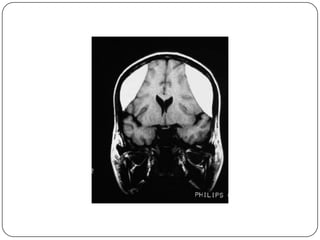

Ofrece una diferenciación entre la sustancia gris y la sustancia blanca

todavía mayor que la TC. Permite la obtención de imágenes directas en

los planos coronal y sagital. LCR aparece negro, aunque el hueso cortical

se muestra negro, la grasa y cuero cabelludo son muy blancas.

Ofrece una diferenciaciónentre la sustancia gris y la sustancia blanca todavía mayor que la TC. Permite la obtención de imágenes directas en los planos coronal y sagital. LCR aparece negro, aunque el hueso cortical se muestra negro, la grasa y cuero cabelludo son muy blancas.